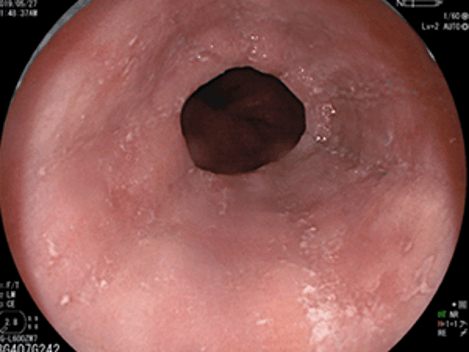

食道中部~下部の静脈瘤が…

EVLとAPCによって治癒して瘢痕化しています。胃カメラ検査をしているととくにご高齢の方で、食道の静脈が局所的に拡張して青白く半球状に盛り上がった状態として観察されることがあります。これは孤立性静脈瘤ともいいますが、先述の食道静脈瘤とは成因や病的意義が異なることもあり、孤立性静脈拡張が正式な名称となっています。